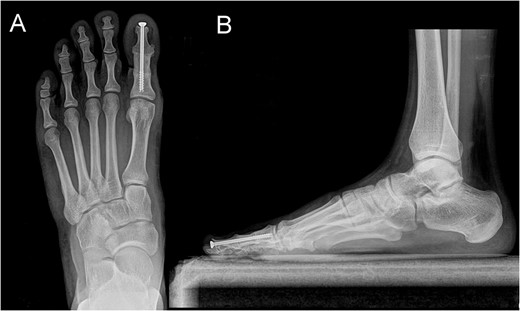

Posterior–anterior (A) and lateral (B) X-ray imaging of the left foot, showing the arthrodesis without signs of recurrence after a follow-up of 30 months.